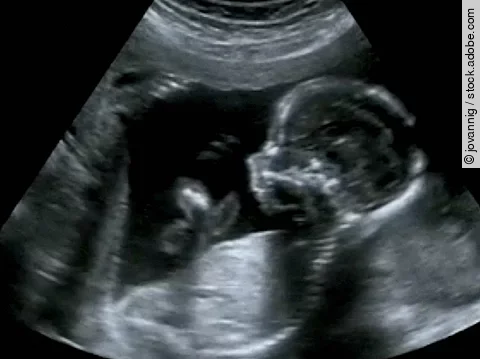

Diese Leitlinie gilt für alle Berufsgruppen, die Schwangere betreuen und in der Schwangerschaft eine fetale Zustandsdiagnostik durchführen. Das Ziel dieser LL ist die Etablierung der Evidenz dafür, ob in einem low-risk Schwangerschafts-Kollektiv die Durchführung des Dopplers oder CTGs das outcome verbessert.